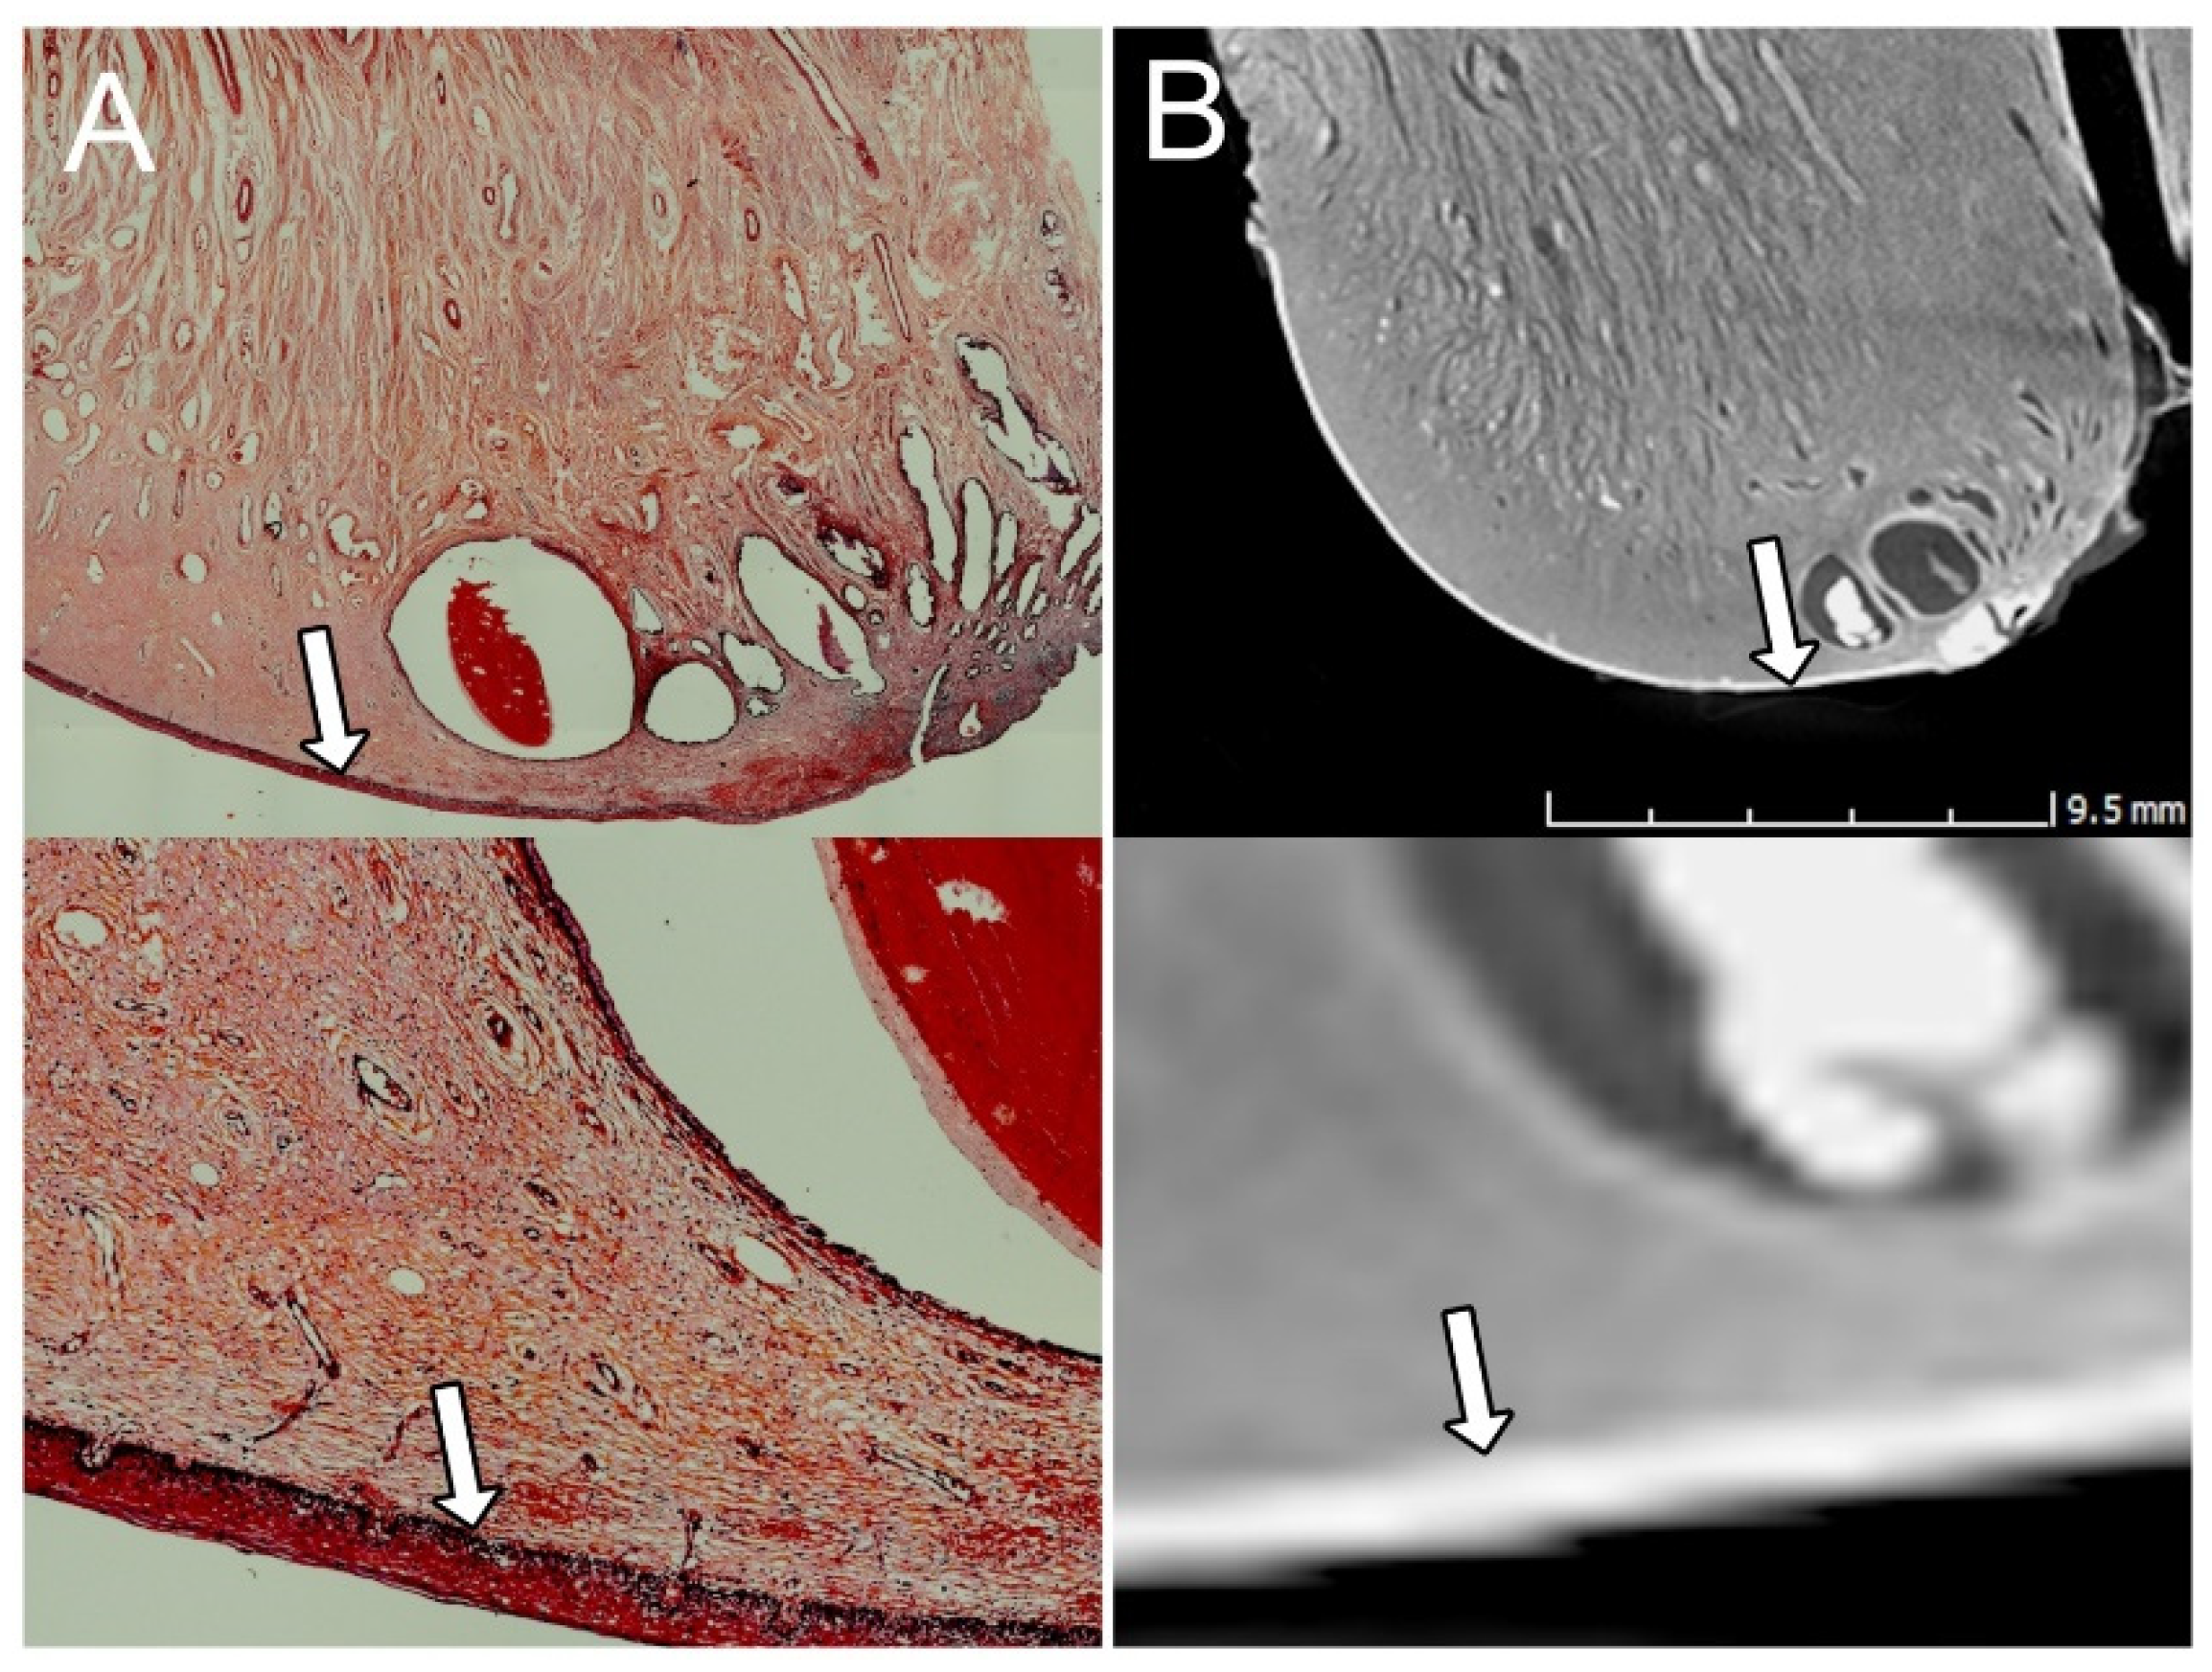

3.4. Transformation of the Endocervical Epithelium—Metaplastic Transformation

3.5. The Endocervical Anatomy